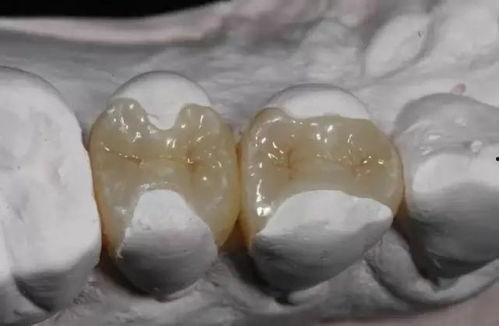

首先,得先弄清楚什么是树脂补牙。简单来说,树脂补牙就是用一种叫做树脂的材料来填补牙齿上的小洞洞,防止细菌入侵,保护牙齿健康。这种材料颜色自然,和牙齿非常搭调,所以很多人都会选择它来修复牙齿。

4. 填充树脂:将树脂材料挤入牙洞,用专用的工具将其塑形,使其与牙齿表面贴合。

6. 抛光:用抛光工具将树脂表面抛光,使其更加光滑。